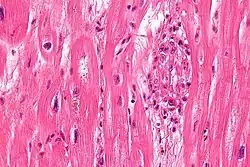

S. pyogenes has a cell wall composed of branched polymers which sometimes contain M protein, a virulence factor that is highly antigenic. The antibodies which the immune system generates against the M protein may cross-react with heart muscle cell protein myosin,[15] heart muscle glycogen and smooth muscle cells of arteries, inducing cytokine release and tissue destruction. However, the only proven cross-reaction is with perivascular connective tissue. This inflammation occurs through direct attachment of complement and Fc receptor-mediated recruitment of neutrophils and macrophages. Characteristic Aschoff bodies, composed of swollen eosinophilic collagen surrounded by lymphocytes and macrophages, can be seen on light microscopy. The larger macrophages may become Anitschkow cells or Aschoff giant cells. Rheumatic valvular lesions may also involve a cell-mediated immunity reaction as these lesions predominantly contain T-helper cells and macrophages.[16]

Chronic rheumatic heart disease (RHD) is characterized by repeated inflammation with fibrinous repair. The cardinal anatomic changes of the valve include leaflet thickening, commissural fusion, and shortening and thickening of the tendinous cords.[16] It is caused by an autoimmune reaction to Group A β-hemolytic streptococci (GAS) that results in valvular damage.[17] Fibrosis and scarring of valve leaflets, commissures and cusps leads to abnormalities that can result in valve stenosis or regurgitation.[18] The inflammation caused by rheumatic fever, usually during childhood, is referred to as rheumatic valvulitis. About half of patients with rheumatic fever develop inflammation involving valvular endothelium.[19] The majority of morbidity and mortality associated with rheumatic fever is caused by its destructive effects on cardiac valve tissue.[18] The complicated pathogenesis of RHD is not fully understood, though it has been observed to use molecular mimicry via group A streptococci carbohydrates and genetic predisposition involving HLA Class II genes that trigger autoimmune reactions.[20]